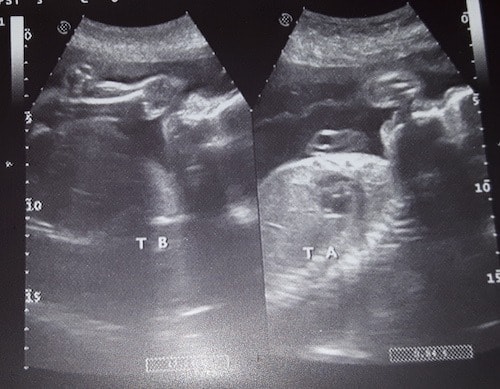

Ultrasound Photos at 26 Weeks Pregnant With Twins